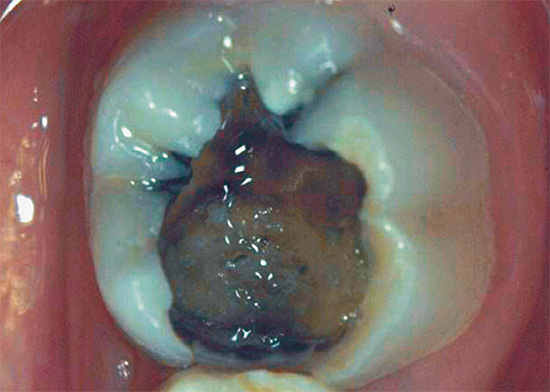

La foto sotto mostra un esempio di carie profonde, in cui la camera pulpare del dente è già molto probabilmente interessata:

La seguente foto mostra un esempio di una cavità così profonda e cariata: